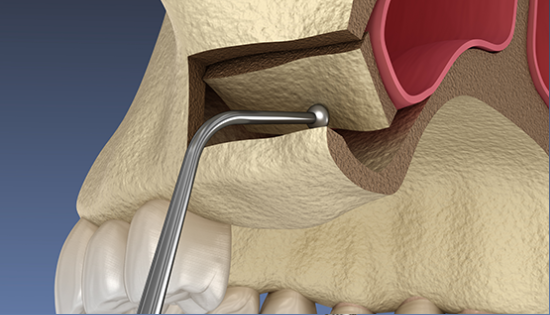

상악동거상술

상악동거상술이란?

부족한 잇몸뼈를 이식하는 시술로 상악동에 있는 얇은 막을 들어 올려 막 아래로 뼈이식을 해서 보강하는 방법입니다.

뼈이식으로 높이를 확보하게 되면 임플란트를 식립해도 상악동을 건드리지 않고

임플란트의 잇몸뼈와 골유착이 잘 되어 안정적으로 시술 할 수 있습니다.

상악동거상술 시술과정

상악동거상술은 고난도 수술로 임플란트 수술 경험이 많은 의료진에게 받는 것이 중요합니다.

• 02

뼈이식 / 임플란트 식립공간 확보

잇몸을 절개하고 난 후 뼈를 넣고 상악동을 들어 올릴만한 작은 통로를 만들어 뼈이식할 공간과 임플란트 식립할 공간을 확보합니다.

• 03

잇몸 뼈이식 시술 진행

들어올린 빈 공간에 뼈를 이식하는데 이때 사용되는 뼈이식 재로로는 자가치아뼈, 자가골, 인공뼈, 합성골 등이 있습니다.